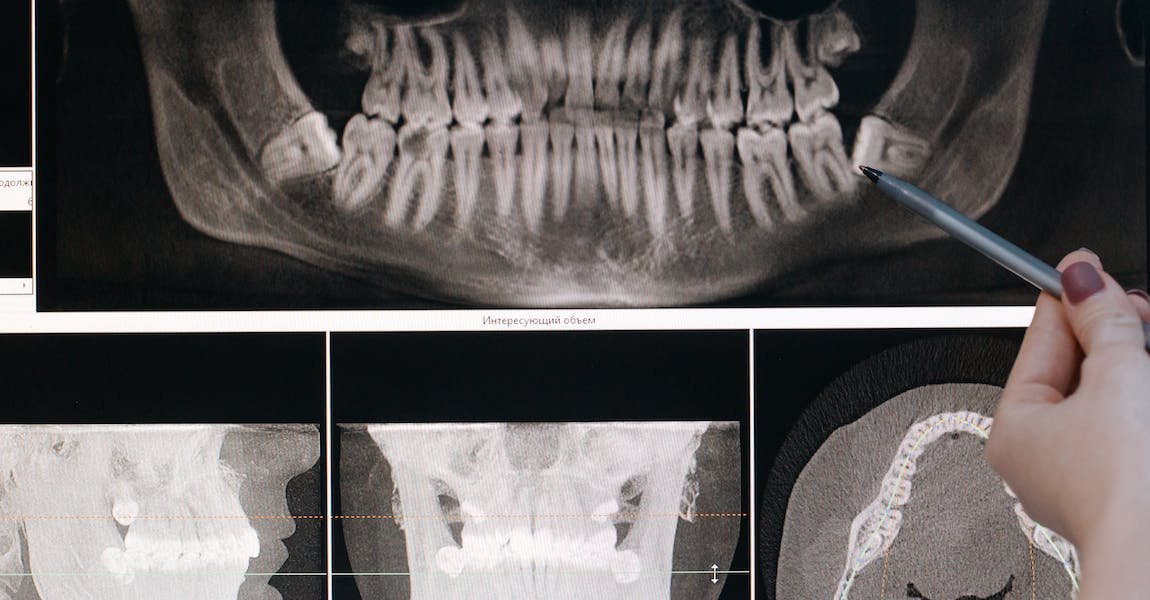

If you feel as though your teeth are well beyond using products like whitening toothpastes, whitening strips, and various other at home treatments, you may consider making an appointment with your dental hygienist to discuss more intense teeth whitening methods done at the dentist’s office.